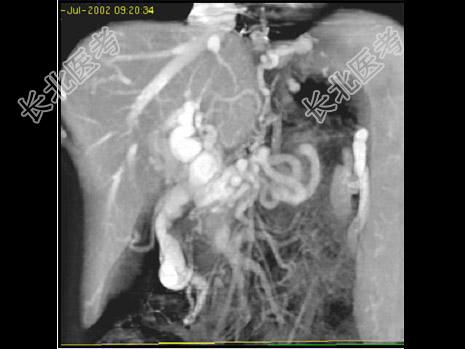

- 单项选择题根据所提供的图像,该病例最可能的诊断为 ( )

A、肝细胞癌

B、梗塞、梗死

C、血行转移

D、门静脉栓塞

E、以上都不是